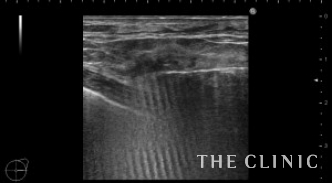

いつも通りベイザーで崩します。

ほとんどの壊死脂肪が除去できました。